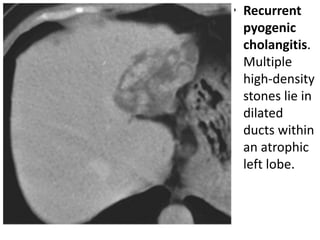

• Recurrent

pyogenic

cholangitis.

Multiple

high-density

stones lie in

dilated

ducts within

an atrophic

left lobe.

• Recurrent pyogeniccholangitis • also referred to as oriental cholangiohepatitis, occurs mainly in South-East Asia or its emigrants. • Characterized by recurrent episodes of cholangitis, bile duct stones, biliary dilatation and strictures. • Infection is due to enteric bacteria that are thought to be responsible for stone formation, although parasites, in particular Clonorchis sinensis, may play a partial role. • The stones are more often intrahepatic, can be very extensive, and are composed of calcium bilirubinate, often visible on CT as high densities within dilated intrahepatic ducts. • US shows duct dilatation and stones that may not shadow. • Cholangiography by any technique shows duct dilatation and multiple stones, which may be widespread or segmental, and duct strictures are common.

• Recurrent pyogenic cholangitis. Multiple high-density stones lie in dilated ducts within an atrophic left lobe.